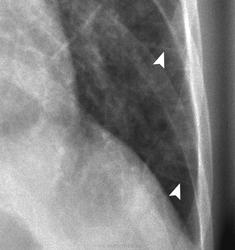

Легочная вено - окклюзионная болезнь (ЛВОБ)- редкое заболевание не установленной этиологии, при котором развитие и прогрессирование ЛГ связано с поражением мелких легочных вен и венул, в том числе тромботического характера.

Ранее ЛВОБ рассматривалась как подтип первичной легочной гипертензии (ПЛГ), однако с учетом вероятных различий в патогенезе ЛВОБ и лечении ПЛГ, в 1998г. ЛВОБ была включена в категорию легочной венозной гипертензии наряду с заболеваниями левых отделов сердца, компрессией легочных вен, фиброзирующим медиастинитом. В 2003г. на 3-м Мировом симпозиуме по ЛГ в Венеции (Италия) на основании сходных патоморфологических проявлений, клинической картины и возможного развития отека легких при назначении простагландинов ЛВОБ и легочный капиллярный гемангиоматоз- доброкачественное неметастазирующее сосудистое образование, приводящее к развитию ЛГ- были объединены в один подтип клинического класса легочной артериальной гипертензии.